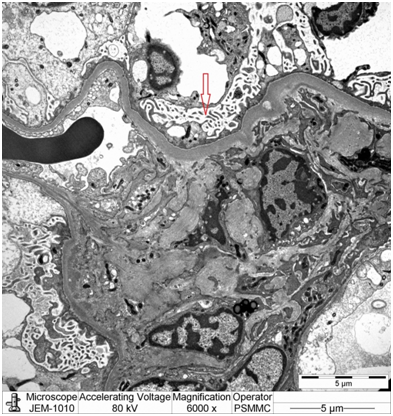

Electron microscopy: Sections stained with Toluidine blue stain showed the renal cortex containing 16 glomeruli, none globally sclerotic. Ultrastructure evaluation showed diffuse epithelial foot processes effacement with microvillus proliferation, mild amounts of electron dense deposits in the mesangial region. The glomerular basement membranes were normal thickness (Figure 2&3).

Figure 2: EM image showing diffuse epithelial foot processes effacement with microvillus proliferation (red arrow).

Focal segmental glomerulosclerosis is a common cause of end stage renal disease requiring renal transplantation [3]. In the pediatric age group, FSGS has a high rate of recurrence (up to 30%) [4-6]. The risk of recurrence in the first graft is high, up to 30%, with graft loss of 40-60% [4,7] while the risk of recurrence in a second graft is 60–100% [8]. Risk factors include: Onset of nephrotic syndrome during childhood, rapid course to ESRD (<3 years), female sex, bilateral nephrectomy, mesangial hypercellularity, presence of FSGS circulating factor [4,5]. The podocin mutation may play a role in pathogenesis and early recurrence of FSGS [3,9]. The presentation of recurrence includes early massive proteinuria (78% during the first month after transplant, often as early as in the first urine from the graft) and sometimes graft failure and hypertension [9]. Proteinuria may herald the development of FSGS even if an early biopsy does not show glomerular abnormalities under light microscopy (as our case). In other words light microscopy will not show any evidence for FSGS and only the presence of diffuse epithelial foot process effacement on electron microscopic examination can prove the diagnosis pathologically.